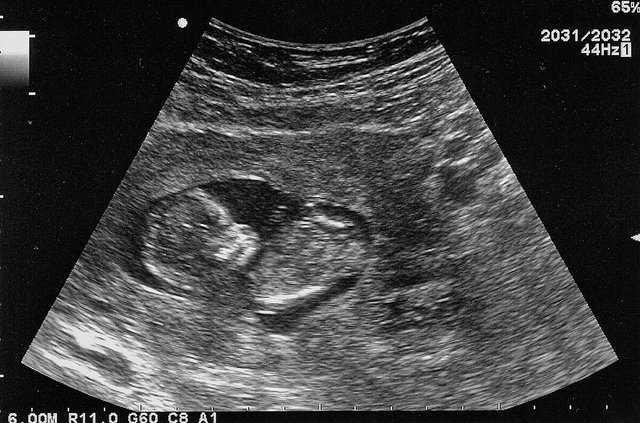

The article, written by Hannah Webster, Communications Manager at Independent Association of Prep Schools in the UK, lays out some of the tragic aspects of sharing today. It argues, quite reasonably, against a world where people post 12-week scans of babies in their mothers’ wombs. “These children,” she says, “have an online presence before they are born – before they even know of their own existence.”